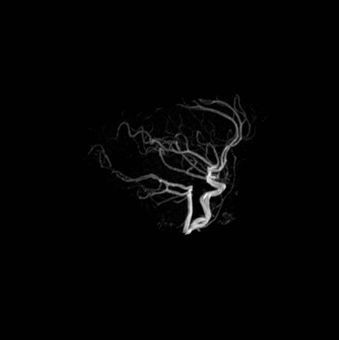

Background: Cavernous hemangiomas are common benign vascular malformations. Their existence in the intraventricular region is very rare. Case Reports: A 43-year old woman with an occipital headache was admitted to the emergency ward. Brain computed tomography scan showed mild hydrocephalus and multiple intraventricular isodense lesions. Imaging findings, especially of Gradient Resonance Echo imaging, were in favor of multiple intraventricular cavernous malformations. Conclusion: This is a rare presentation of multiple cavernous malformation as occipital headache without needing surgical intervention in this phase. Coexistence of periventricular plaques like Radiologically isolated syndrome of Multiple sclerosis is another unique aspect in this report. [GMJ.2017;6(1):61-65]